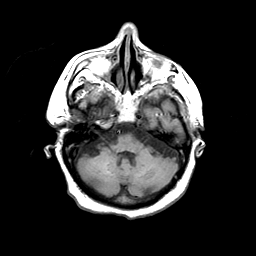

Basal Ganglia Calcification: T1-weighted MR -- Slice #4

[Home][Help][Clinical] Slice 4